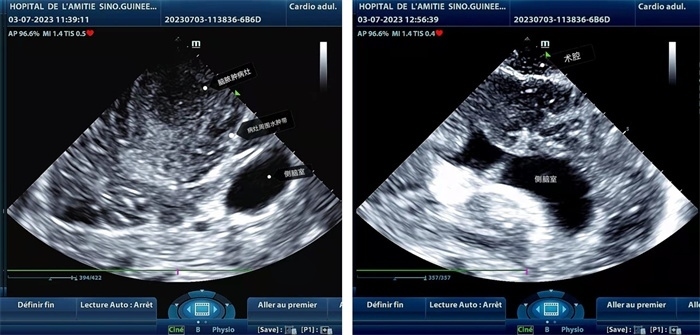

左圖顯示術(shù)中超聲見(jiàn)囊實(shí)性病變,大小約為4x4x3cm,病灶周?chē)X組織水腫明顯;右圖為病灶切除后,術(shù)中超聲示術(shù)腔無(wú)病變殘留

手術(shù)中,張國(guó)濱在超聲科顧秀娟的幫助下,運(yùn)用顱腦術(shù)中超聲技術(shù),通過(guò)將一次性保護(hù)套的超聲探頭置于腦組織表面,實(shí)時(shí)觀察病變的位置和形態(tài),進(jìn)一步確認(rèn)最佳手術(shù)路徑。術(shù)中超聲顯示,病變位于左額頂葉,大小約為4x4x3cm,邊界清晰,呈囊實(shí)性,周邊腦組織水腫明顯。最終,病灶順利切除,診斷為腦膿腫,并通過(guò)超聲檢測(cè)確認(rèn)術(shù)腔無(wú)病變殘留、無(wú)出血,為患者術(shù)后恢復(fù)提供了良好的保障。